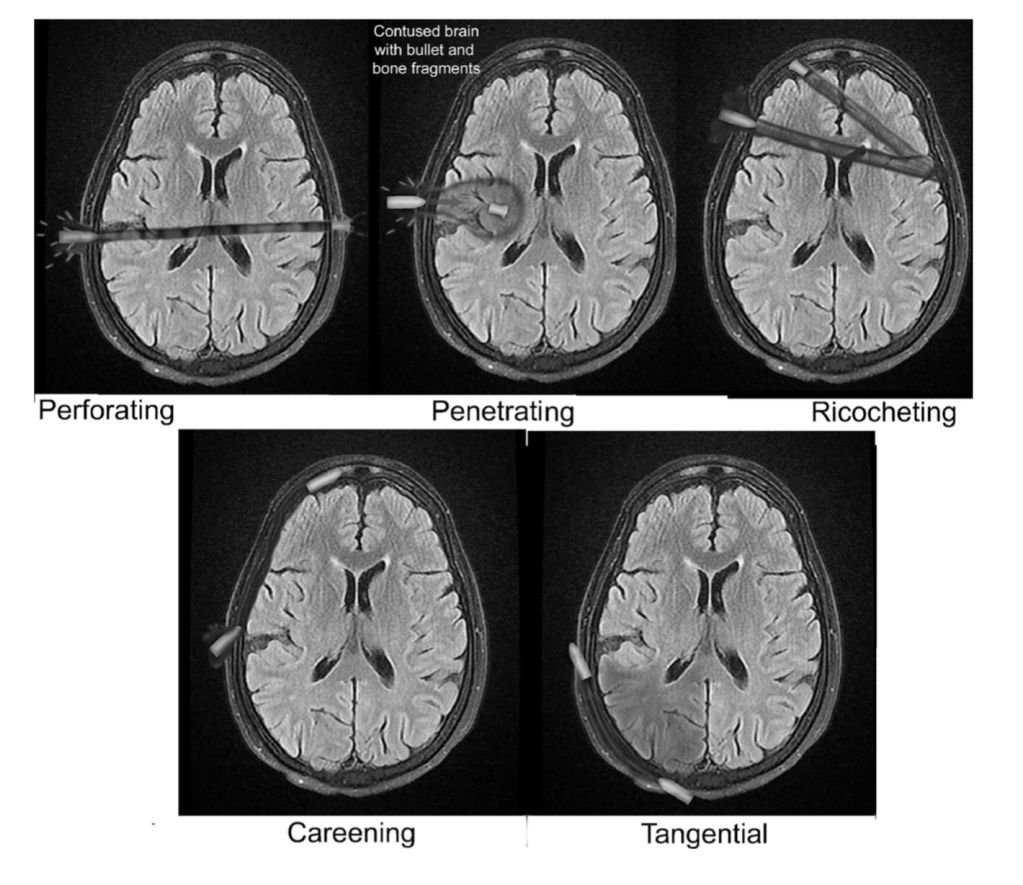

- Wound types (Vakil, Emerg Radiol, 2017)

- Penetrating: entry wound with no exit wound

- Perforating: entry and exit wound with tract through the brain parenchyma

- Tangential: strikes the head obliquely without penetrating the brain tissue but may result in scalp lacerations, skull fractures, or cerebral contusions

- Ricochet: penetrating bullet that may bounce off the inner table of the skull one or more times

- Careening: penetrates the skulls and travels along the periphery of the cortex without entering parenchyma but has the potential to damage the dural venous sinuses